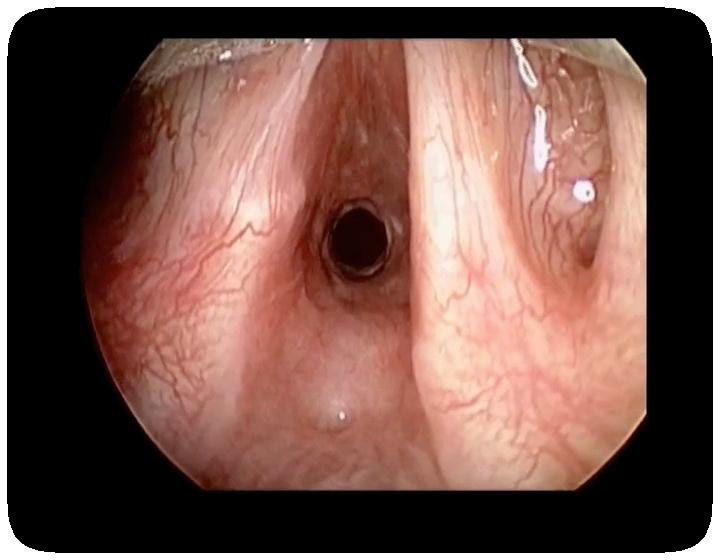

Figure 5

Direct laryngoscopy intraoperative view of subglottic stenosis in a patient with GPA (reprinted from Wolter NE, Ooi EH, Witterick IJ. Intralesional corticosteroid injection and dilatation provides effective management of subglottic stenosis in Wegener’s granulomatosis. Laryngoscope. 2010;120(12):2452–5. © 2010, with permission from John Wiley & Sons).

SGS is best studied on CT scan (fig. 4 and 5) but must also be evaluated clinically by flexible nasolaryngoscopy. Interestingly, the lesion is usually segmental and located 1 to 2 cm below the vocal cords, probably because it represents the junction between 2 embryological buds or growth centres. Biopsy of the lesions can be revealing in more than half of cases, but endoscopy and biopsy of SGS may be risky in such patients. These invasive procedures can trigger a local inflammatory reaction, worsen the stenosis, and/or result in detached necrotic debris which is then inhaled, during the procedure itself or soon after. Spirometry may reveal blunting of the inspiratory curve, but the diagnosis should not rely solely on this modality.

SGS can be life-threatening and should therefore be addressed early. Systemic treatment remains mandatory and is usually effective for generalised or severe GPA, but corticosteroids and conventional immunosuppressants usually have minimal effect on SGS. Corticosteroids can be transiently effective and remain indicated in patients with acute inflammatory exacerbations of SGS, but are unable to reverse scarring and fibrotic SGS. Data on cyclophosphamide or rituximab effects on SGS are scant [41, 48]. One study reported some efficacy of rituximab in 1 of only 2 patients and after a delay of 4 months post-infusion [69]; some responses were noted in a more recent study in all of the 11 patients who received this monoclonal antibody [70]. A potential limitation of these studies is the definition of responsiveness for SGS. Long-term follow-up, a minimum of 1 to 2 years, seems necessary to evaluate the response appropriately and determine whether rituximab (or another systemic) treatment can really limit the need for repeat dilatations.

Local management begins with clearance of secretions and meticulous care of the sino-nasal tract to avoid subsequent airway obstruction [41]. Crust formation may also be reduced with a humidified home environment. Given that many GPA patients with SGS also have laryngopharyngeal reflux, gastric acid suppression must be considered [71]. Surgical and/or endoscopy management may be necessary if respiratory symptoms progress. A number of procedures have been reported, including CO2 laser ablation [72], nitinol stenting [73] and intralesional corticosteroid injection and dilatation (ILCD) [33, 41, 71, 74]. Some authors have noted increased cicatricial scarring and poor post-operative outcomes in patients receiving CO2 laser treatment [33, 41, 71]. The most effective local procedure for treatment of SGS appears to be ILCD, with bougies or balloon dilators, followed by cold steel scar lysis with a sickle knife or endolaryngeal microscissors combined with in situ corticosteroid injection [33, 41, 75]. However, most GPA patients with SGS require several repeat procedures, in a recent study an average of 3 times at a mean interval of 11.5 months [74]. In these studies ILCD was indicated on the basis of symptoms regardless of disease severity and avoided tracheotomy [41, 74]. Spirometry parameters (forced expiratory volume in 1 second, forced vital capacity increase and peak expiratory flow rate) may be used to assess the response more objectively. Patients’ perceived improvement in breathing, along with a decrease in the rate of chest infections following the procedure(s), helps in evaluating the benefit of dilation(s). The utility of local applications of mitomycin-C, concomitant with dilations, is not well determined but is used on a regular basis by several groups. Reconstructive laryngotracheal surgery has been successful but is reserved for very severe cases or with failed endoscopy management and restricted to specialised centres [33, 76]. To ensure optimal success and minimal risk of complications, this surgical procedure must be performed only when the disease is in a quiescent phase, to avoid recurrence at the site, and in patients off, or taking only a minimal dose of, corticosteroids, to allow healing of the anastomosis.